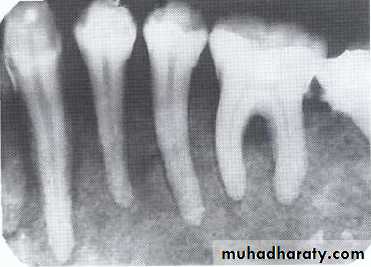

Traumatic cyst*Mandible > Maxilla. <20 years of age.

*Asymptomatic, expansile, associated with history of trauma. *Extend between the roots of teeth with scalloped border .

*Aspiration is not productive, empty cavity.